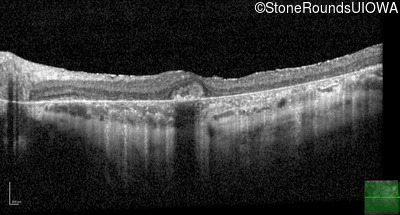

Age at visit: 30 years

This 30 year old man first noticed poor vision in dim light when he was five years old. His visual acuity began to fall in his early 20's.

Macular Disease WDR19 His344Arg CAT>CGT Ser485Ile AGT>ATT AR